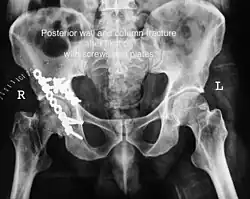

Posterior wall fracture fixed with screws and plate -

Posterior column and wall fixed using screws and plates